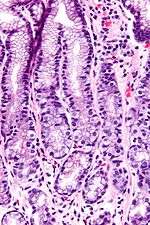

Histomorphology

G cells have a distinctive microscopic appearance that allows one to separate them from other cells in the gastric antrum; their nuclei are centrally located in the cell. They are found in the middle portion of the gastric glands.